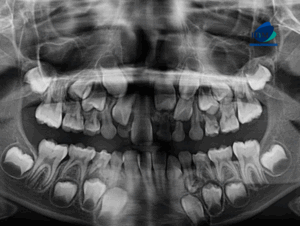

Paciente masculino de 8 años de edad acude al Instituto de Diagnóstico Maxilofacial – IDM (Miraflores) para evaluación imagenológica.En la radiografía panorámica (Figura 1), se